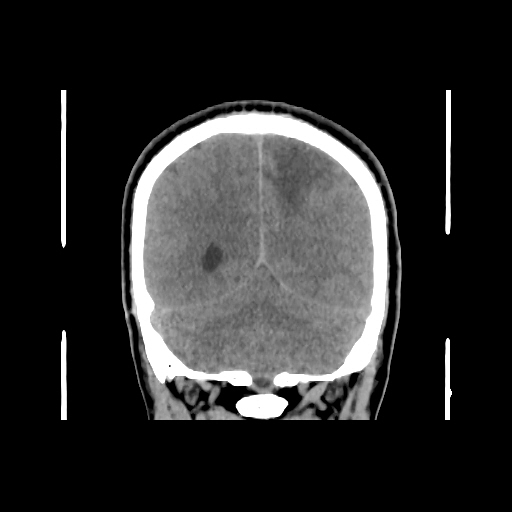

A 35 years old man CT head